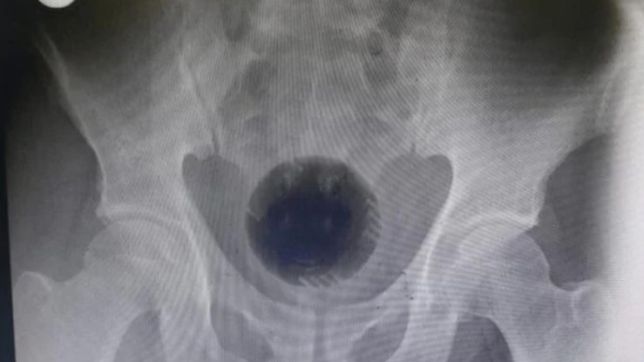

Um homem de 51 anos, que não teve o nome revelado, teve que passar por uma cirurgia de emergência em um hospital da Jordânia após ficar com uma bola de plástico presa no seu reto. As informações do caso foram pelo jornal britânico The Sun.

Os médicos chegaram a tentar remover o objeto manualmente e até mesmo tentaram empurrar a bola pelo estômago do paciente, mas não obtiveram sucesso.

“Infelizmente, o corpo estranho estava firmemente preso na pélvis, movendo a bola impactada para cima”, escreveram os médicos no artigo que descreveu o caso.

Dada as tentativas frustradas da equipe médica, eles optaram por uma cirurgia, que durou sete horas, onde a bola foi cortada em três pedaços menores com a ajuda de uma furadeira elétrica inserida no ânus do paciente.